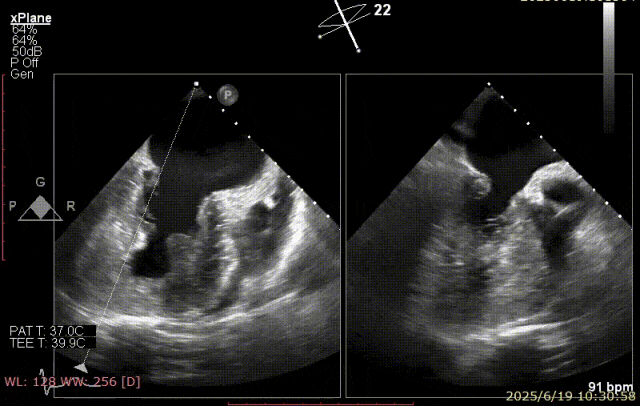

术前超声

患者术前 TEE 可见 P3 区脱垂二尖瓣环前后径(AP)约 37 mm,CC 径约 41 mm,瓣叶无明显钙化及裂隙,后瓣瓣尖探及一长约 9 mm 短带样回声漂附,二尖瓣口面积约 5.3 cm²。

经我院心脏超声检查提示:左房室增大伴二尖瓣后瓣脱垂(P3 区,腱索断裂)并重度关闭不全(Carpentier IIb 型,反流分级 4+);符合高血压性心脏病改变;少至中等量心包积液;左室舒张功能降低,收缩功能测定在正常范围并呈假性高排表现。